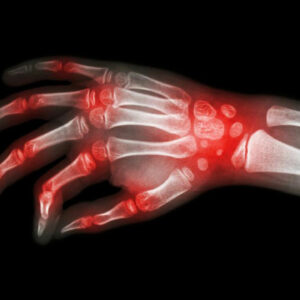

Fibromyalgia is a form of arthritis which at times can be challenging to diagnose. Therefore there are certain symptoms that you must know about so that you can immediately seek the counsel of a specialist. Chronic burning – Burning or sharp pain in muscles, muscle spasms, or tightness in different parts of the body.